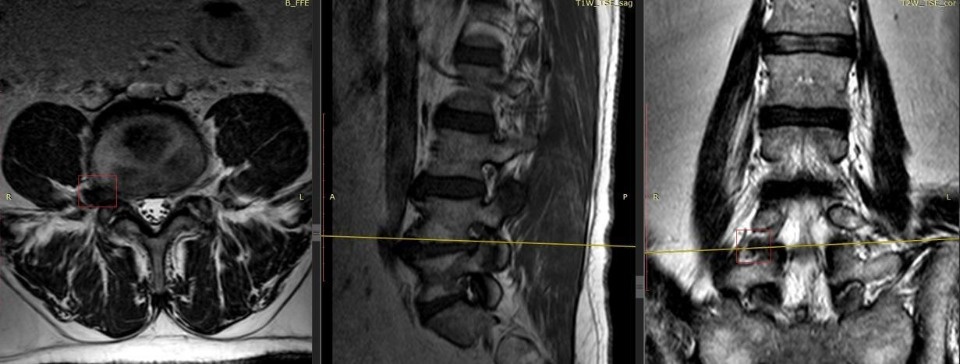

Затруднения в осмотре пациента вызывал выраженный болевой синдром. МРТ показала, что у мужчины экстрафораминальная грыжа межпозвонкового диска между 4 и 5 поясничными позвонками справа с грубой компрессией спинального корешка.